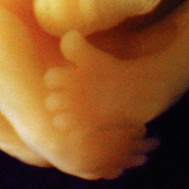

All essential body parts are present and accounted for. Your ankles have formed, your arms are long and bend at the elbows. With basic physiology in place, rapid growth and weight gain are the next steps![1]

You are intricately detailed, but still so tiny, only about 3/4 inch (20 millimeters) long.[2]